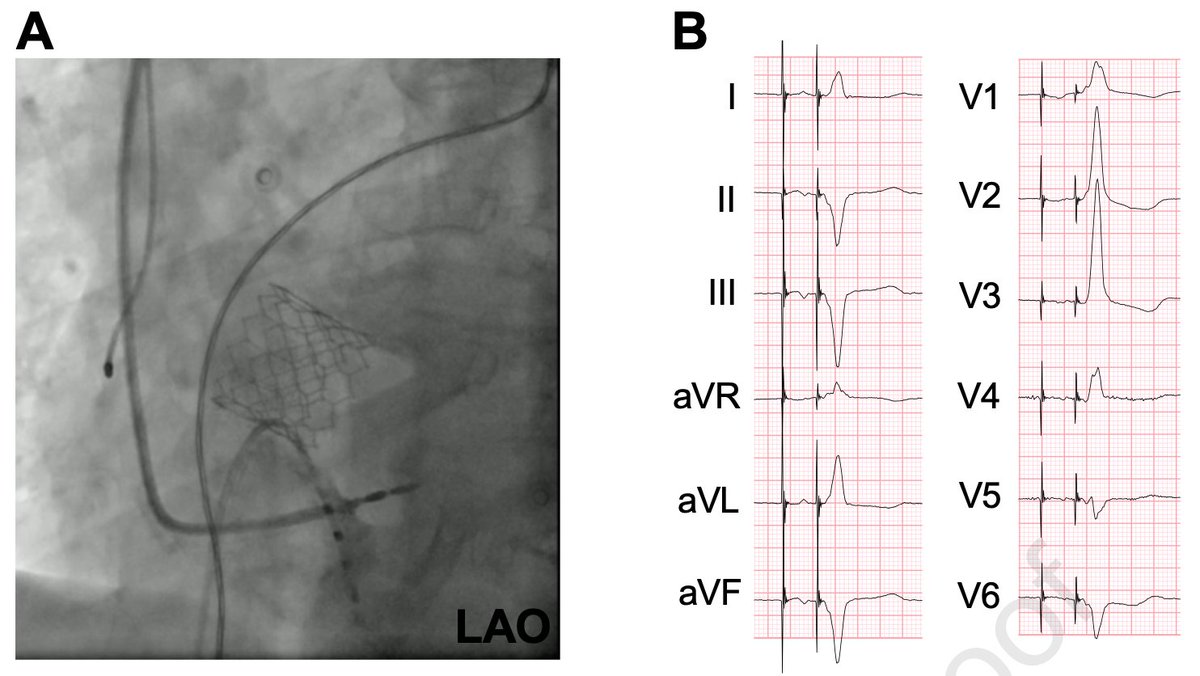

Early sudden distal conductor fracture of a stylet-driven lead implanted for left bundle branch area pacing heartrhythmcasereports.com/article/S2214-…